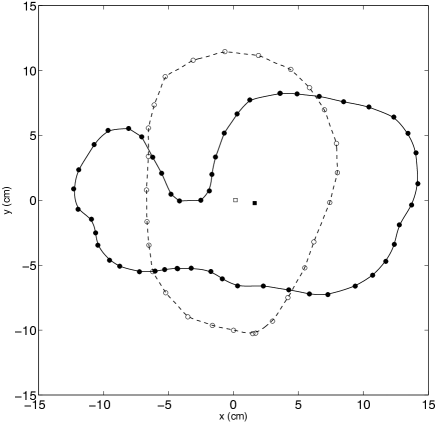

3.1 Interpolation of Chorionic Plate Outlines

Figure 1 shows typical fits to the data points of chorionic plate outlines obtained with the method described in A. Two types of outlines are shown: one with a single-valued and one with a multi-valued radius. A single-valued radius means that a line emanating from the centroid intersects every point on the perimeter only once, while a multi-valued radius function may intersect the perimeter more than once. In the latter case, the perimeter folds back on itself, and the corresponding chorionic plate has lobes or some other irregular shape. Note the irregular spacing of the points along the perimeter, as described in Sec. 2.1. The outline with the single-valued radius has a regular shape, so relatively few data points are needed. However, the outline with the multi-valued radius has intervals where more points are needed to describe regions of greater curvature, which can occur for a small protrusion or, as in this case, a large morphological entity such as a lobe. This is reflected in the number of terms that must be included in the Fourier series to produce an accurate interpolation. The series for the outline with the single-valued radius required fewer terms than that for the outline with the multi-valued radius because regions of larger curvature mean that more rapidly varying trigonometric functions must be included in the interpolation.